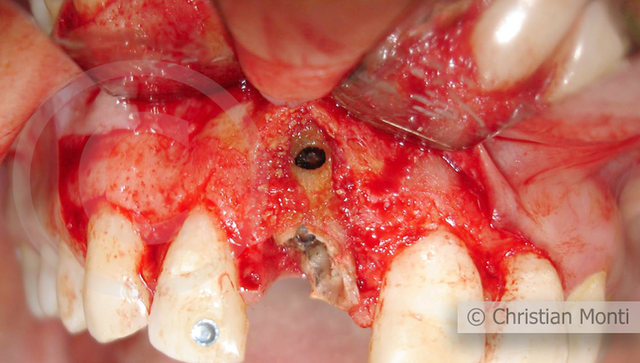

EDENTULIA SINGOLA

Impianto in sostituzione di un incisivo superiore